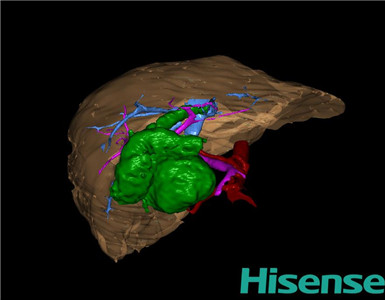

CT结果输入海信CAS系统后行3D重建及手术规划后,于2015-8-15全麻下行“胆总管囊肿切除+胆囊切除+胆总管-空肠吻合术”手术治疗:

术前三维重建及手术方案设计:

将0.625mm双源薄层CT资料的静脉期和动脉期Dicom格式文件导入海信CAS系统。

通过调节窗宽窗位调整CT序号,对肝实质,胆囊,下腔静脉,肿瘤,肝动脉、门静脉及肝静脉等进行三维重建;系统自动计算肝脏体积。

术前手术方案的规划。

术前三维重建:

重建图片